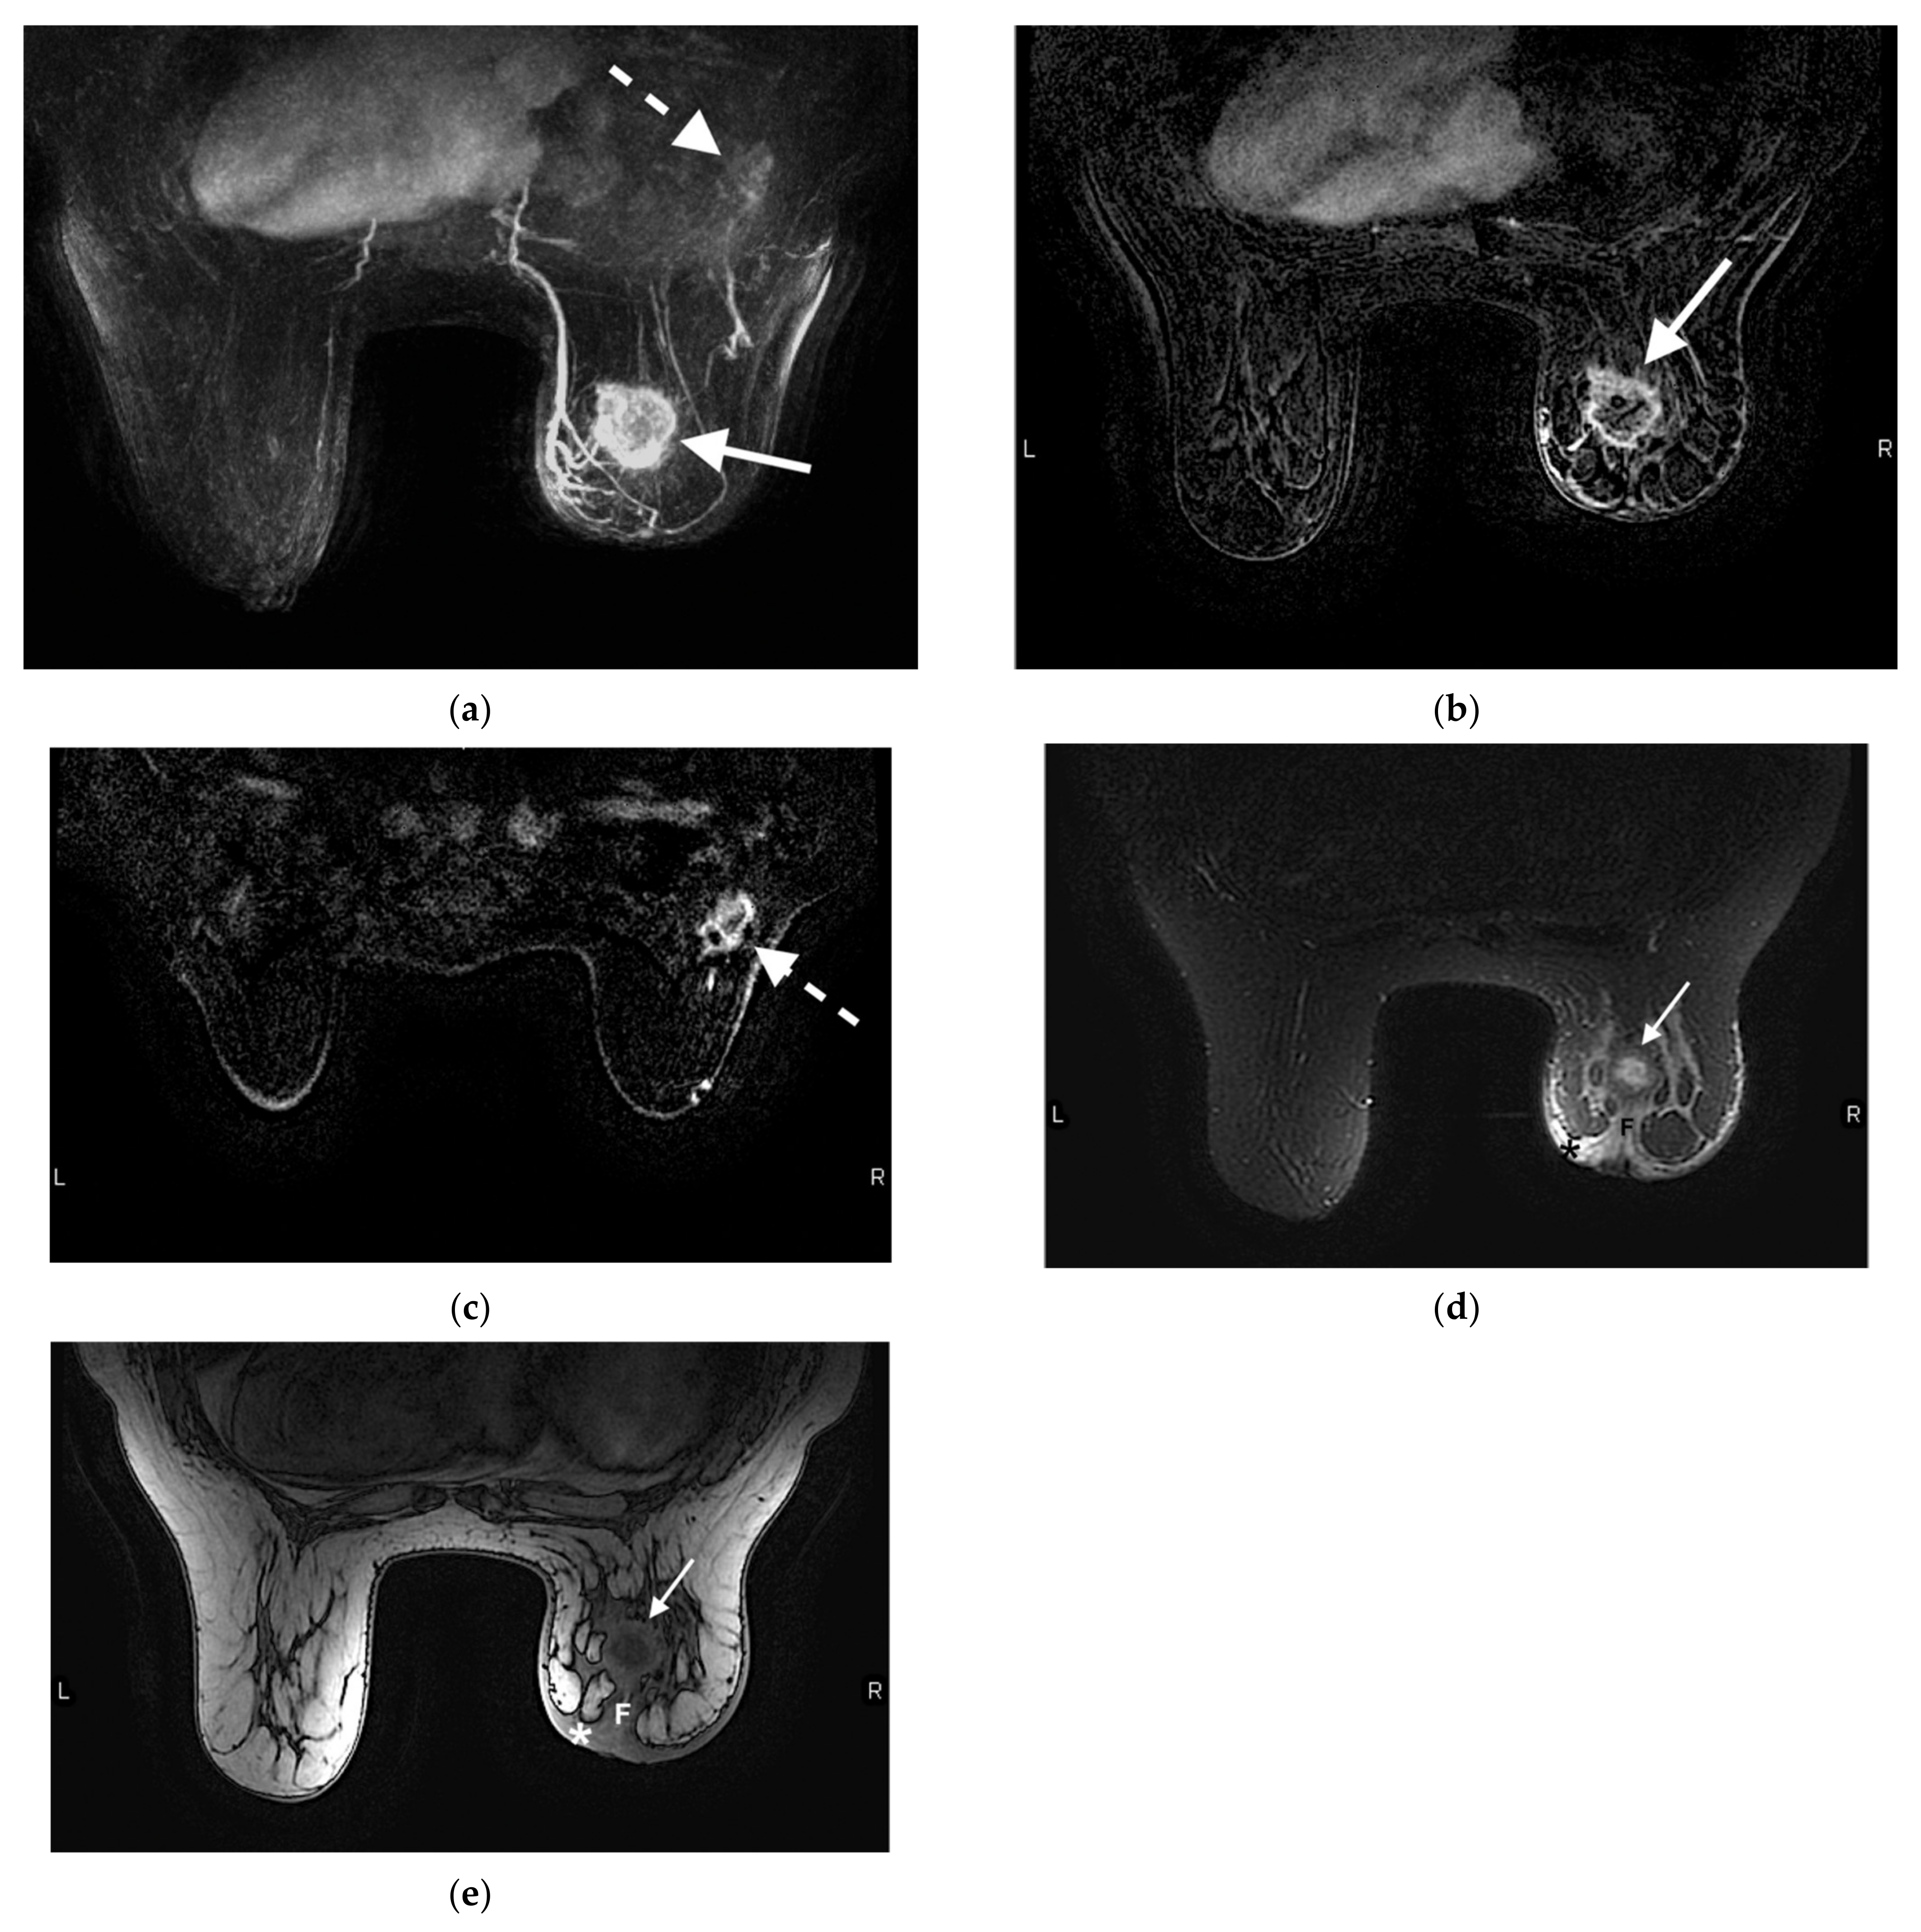

- Brennan, M.E.; Houssami, N.; Lord, S.J.; Macaskill, P.; Irwig, L.; Dixon, J.M.; Warren, R.M.; Ciatto, S. Magnetic resonance imaging screening of the contralateral breast in women with newly diagnosed breast cancer: Systematic review and meta-analysis of incremental cancer detection and impact on surgical management. J. Clin. Oncol. 2009, 27, 5640–5649. [Google Scholar] [CrossRef] [PubMed] [Green Version]

- Plana, M.N.; Carreira, C.; Muriel, A.; Chiva, M.; Abraira, V.; Emparanza, J.I.; Bonfill, X.; Zamora, J. Magnetic resonance imaging in the preoperative assessment of patients with primary breast cancer: Systematic review of diagnostic accuracy and meta-analysis. Eur. Radiol. 2012, 22, 26–38. [Google Scholar] [CrossRef] [PubMed]

- Benveniste, A.; Ortiz-Perez, T.; Ebuoma, L.; Sepulveda, K.; Severs, F.; Roark, A.; Wang, T.; Sedgwick, E. Is breast magnetic resonance imaging (MRI) useful for diagnosis of additional sites of disease in patients recently diagnosed with pure ductal carcinoma in situ (DCIS)? Eur. J. Radiol. 2017, 96, 74–79. [Google Scholar] [CrossRef] [PubMed]

- Kuhl, C.K.; Strobel, K.; Bieling, H.; Wardelmann, E.; Kuhn, W.; Maass, N.; Schrading, S. Impact of Preoperative Breast MR Imaging and MR-guided Surgery on Diagnosis and Surgical Outcome of Women with Invasive Breast Cancer with and without DCIS Component. Radiology 2017, 284, 645–655. [Google Scholar] [CrossRef] [Green Version]

- Lobbes, M.B.; Vriens, I.J.; Van Bommel, A.C.; Nieuwenhuijzen, G.A.; Smidt, M.L.; Boersma, L.J.; Van Dalen, T.; Smorenburg, C.; Struikmans, H.; Siesling, S.; et al. Breast MRI increases the number of mastectomies for ductal cancers, but decreases them for lobular cancers. Breast Cancer Res. Treat. 2017, 162, 353–364. [Google Scholar] [CrossRef] [PubMed] [Green Version]

- Croshaw, R.; Shapiro-Wright, H.; Svensson, E.; Erb, K.; Julian, T. Accuracy of clinical examination, digital mammogram, ultrasound, and MRI in determining postneoadjuvant pathologic tumor response in operable breast cancer patients. Ann. Surg. Oncol. 2011, 18, 3160–3163. [Google Scholar] [CrossRef] [PubMed]

- Sheikhbahaei, S.; Trahan, T.J.; Xiao, J.; Taghipour, M.; Mena, E.; Connolly, R.M.; Subramaniam, R.M. FDG-PET/CT and MRI for Evaluation of Pathologic Response to Neoadjuvant Chemotherapy in Patients With Breast Cancer: A Meta-Analysis of Diagnostic Accuracy Studies. Oncologist 2016, 21, 931–939. [Google Scholar] [CrossRef] [PubMed] [Green Version]

- Mukhtar, R.A.; Yau, C.; Rosen, M.; Tandon, V.J.; Hylton, N.; Esserman, L.J. Clinically meaningful tumor reduction rates vary by prechemotherapy MRI phenotype and tumor subtype in the I-SPY 1 TRIAL (CALGB 150007/150012; ACRIN 6657). Ann. Surg. Oncol. 2013, 20, 3823–3830. [Google Scholar] [CrossRef] [Green Version]

- Denis, F.; Desbiez-Bourcier, A.; Chapiron, C.; Arbion, F.; Body, G.; Brunereau, L. Contrast enhanced magnetic resonance imaging underestimates residual disease following neoadjuvant docetaxel based chemotherapy for breast cancer. Eur. J. Surg. Oncol. 2004, 30, 1069–1076. [Google Scholar] [CrossRef]

- Schrading, S.; Kuhl, C.K. Breast Cancer: Influence of Taxanes on Response Assessment with Dynamic Contrast-enhanced MR Imaging. Radiology 2015, 277, 687–696. [Google Scholar] [CrossRef]

- Chen, J.-H.; Bahri, S.; Mehta, R.S.; Carpenter, P.M.; McLaren, C.E.; Chen, W.-P.; Fwu, P.T.; Hsiang, D.J.B.; Lane, K.T.; Butler, J.A.; et al. Impact of factors affecting the residual tumor size diagnosed by MRI following neoadjuvant chemotherapy in comparison to pathology. J. Surg. Oncol. 2014, 109, 158–167. [Google Scholar] [CrossRef] [PubMed] [Green Version]

- Reig, B.; Lewin, A.A.; Du, L.; Heacock, L.; Toth, H.K.; Heller, S.L.; Gao, Y.; Moy, L. Breast MRI for Evaluation of Response to Neoadjuvant Therapy. Radiographics 2021, 41, 665–679. [Google Scholar] [CrossRef] [PubMed]